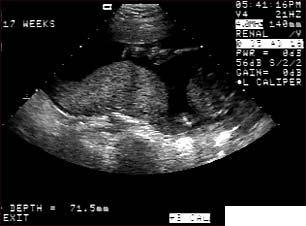

Ecografia fetala